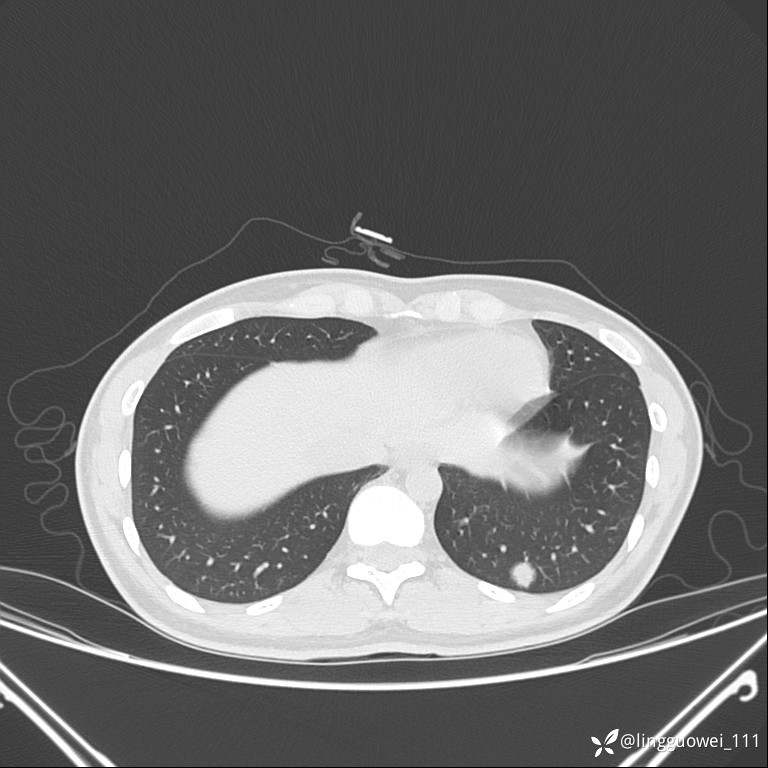

年轻女性咳嗽,CT发现肺结节,良性还是恶性?(4天后公布结果)

患者性别:女

患者年龄:26岁

主诉:咳嗽来诊,结节性质不明。

肺毛细血管瘤 (2)